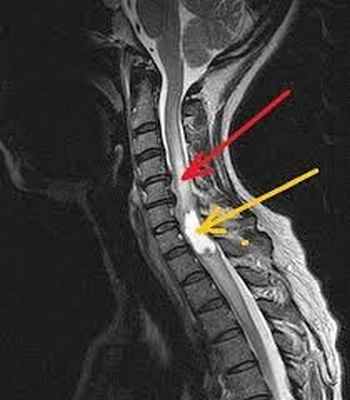

При длительных и упорных болевых проявлениях со стороны позвоночника, кроме МРТ шеи иногда приходится делать и МРТ исследование грудного отдела. Это нужно для дифференциальной диагностики. Пример — метастатическое поражение грудного отдела могут давать боли и в шее:

: